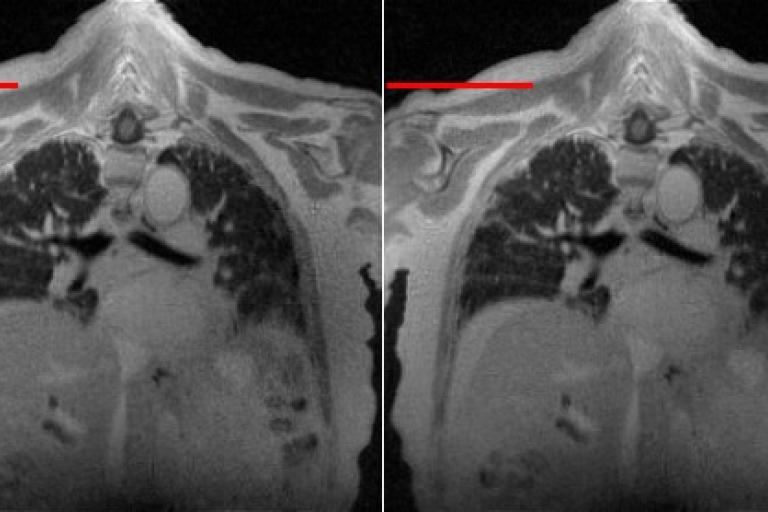

One of the research objects in the lab is on the development of deep-learning algorithms for cardiopulmonary MRI processing, especially the development of unsupervised learning algorithms. We are interested in 2D and 3D cardiopulmonary MRI reconstruction, denoising, super-resolution and segmentation. In this objective, we have developed several algorithms such as G-SToRM, MoCo-SToRM, V-SToRM for real-time cardiopulmonary processing. These work on real-time cardiopulmonary processing wothe best paper award in 2020, and the best paper award finalist in 2021 at IEEE International Symposium on Biomedical Imaging (IEEE ISBI). We've also extended the above algorithms for better performances based on recent advances in deep learning such as the inclusion of Spatial Transformer Networks (STN), Implicit Neural Representations (INR), Graph Convolutional Network (GCN),Kernel method into the algorithms.

The second line of research in the lab is on the development of novel fast 2D and 3D cardiopulmonary MRI pulse sequences for the care of patients with congenital and acquired heart diseases. This includes the development of fast 2D or 3D sequences for myocardial quantification, such as multi-tasking sequences, MR fingerprinting sequences. We are also interested in developing robust fast 3D MR angiography sequences, 3D lung sequences based on ultra-short echo time (UTE) sequences and non-contrast-enhanced 3D whole-heart sequences